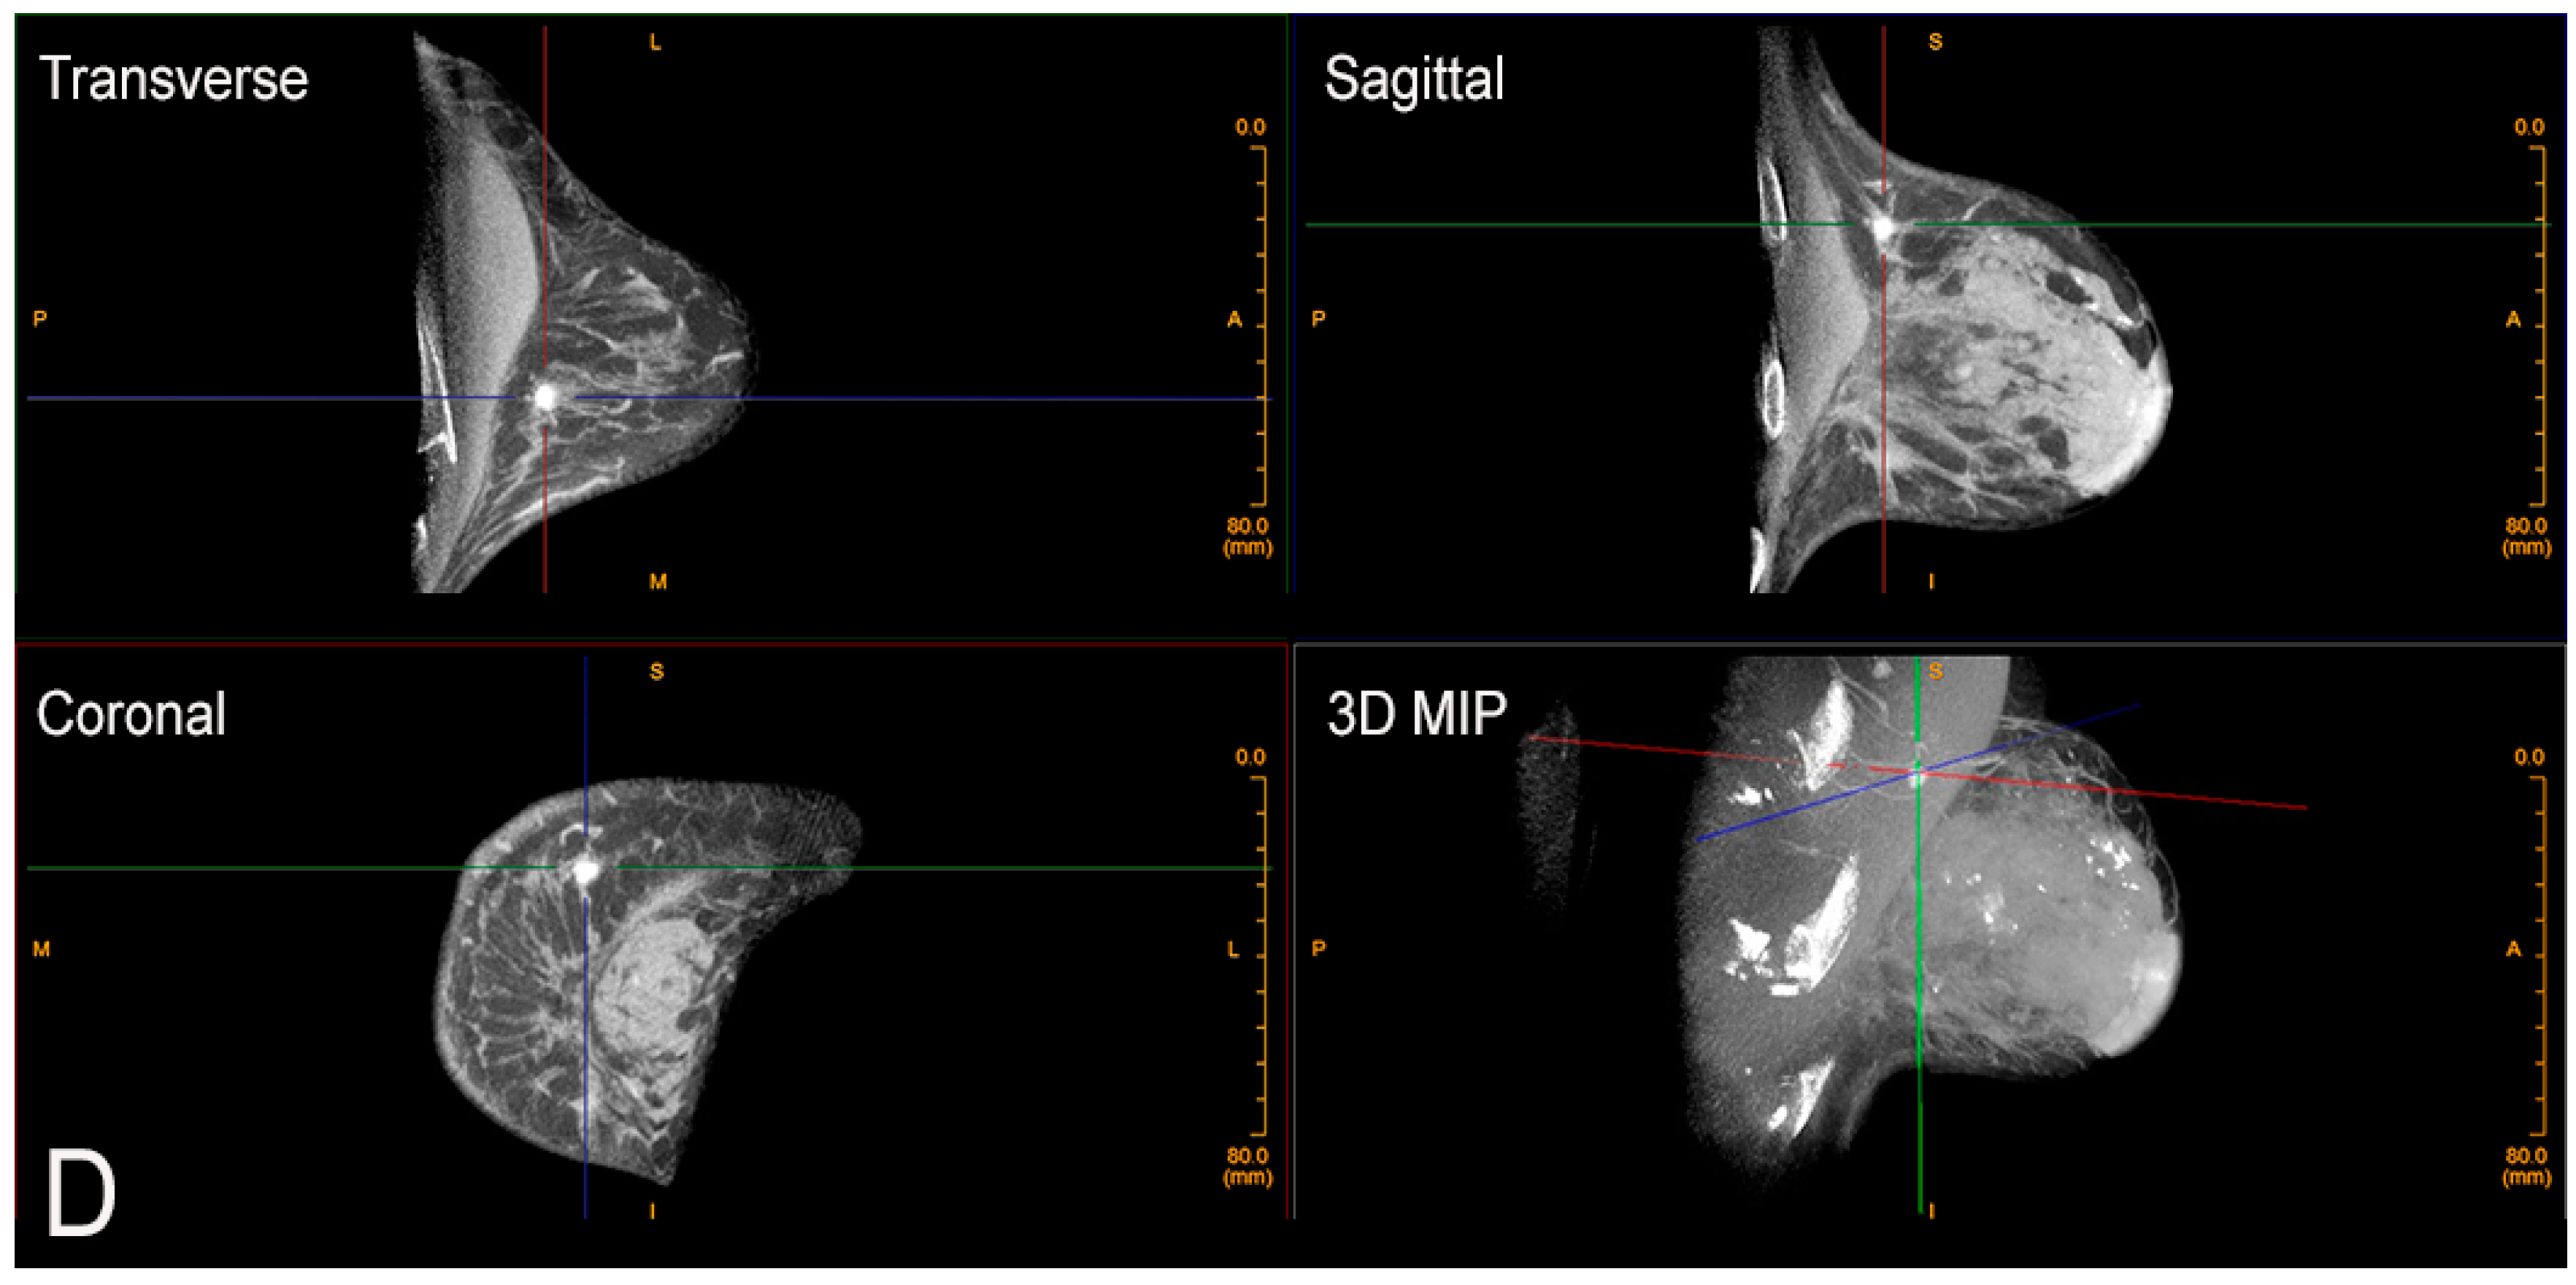

2. Cone-Beam Breast Computed Tomography